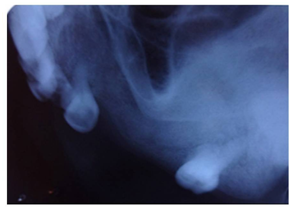

The investigations advised included the complete blood picture, intraoral periapical radiograph, maxillary occlusal view, panoramic radiograph and CBCT. Periapical radiograph and maxillary left lateral topographical occlusal view a revealed diffuse patchy radiolucency in region of 26, 27 along with multiple flecks of fine calcifications and hypercementosis was seen with respect to 28 (Figure 2) (Figure 3). Panoramic view revealed radiopacity extending from 24 to tuberosity and encroaching onto the maxillary sinus (Figure 4). To make out the exact extent of the lesion CBCT imaging was planned. CBCT sections showed mixed radiopaque radiolucent (predominately radiopaque) lesion, with well defined borders, extending from 24 till tuberosity region (Figure 5) measuring anteroposteriorly 4cm ,superoinferiorly 5cm ,and mesiodistally around 2.5cm in dimension. The pterygoid plates though intact, the lesion however did superimpose on the maxillary sinus. No secondary reaction in the sinus could be appreciated. With a clearer picture on the extent of the lesion, we took the next step towards the management.

Figure 2 The complete blood picture, intraoral periapical radiograph, maxillary occlusal view.

Figure 3 Periapical radiograph and maxillary left lateral topographical occlusal view.